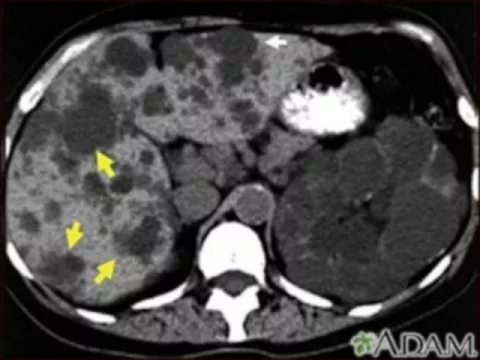

Poliquistosis renal

La PQR es una enfermedad o trastorno de los riñones que está causada por un defecto genético hereditario, que se transmite de padres a hijos, la pueden tener algunos hijos y otro no, en la que se forman sacos llenos de agua (quistes) en los riñones, aumentan de tamaño y su tejido funcional disminuye. Tiene 2 formas hereditarias la autosómica dominante y autosómica recesiva.

La 50% de las personas con PQR tienen quistes en el hígado.

• TC abdominal

• Ecografía abdominal